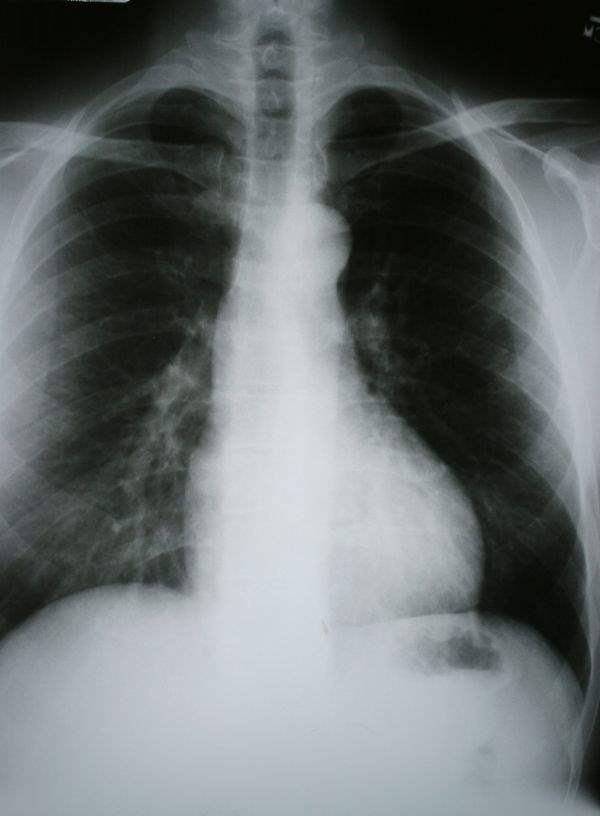

KOAH bir grup akciğer hastalığının adıdır ve açılımı kronik

obstrüktif akciğer hastalığıdır. KOAH hastaları nefes almakta zorlanır, sürekli

öksürürler ve belirtiler bazen akut ataklar şeklinde alevlenebilir. KOAH ilerleyen